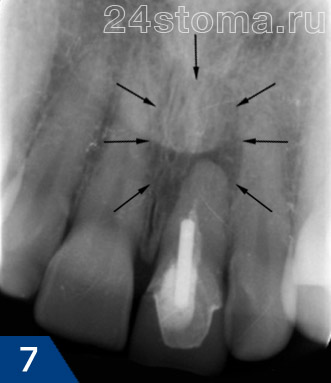

в результаті розгойдують рухів зуб набуває рухливість, після чого витягується з лунки. Дуже важливо оглянути лунку зуба після видалення на предмет наявності осколків. Всі рухомі фрагменти кісткової тканини повинні бути удалени.Еслі зуб видаляється на тлі періодонтиту, при якому в області верхівки кореня утворюється кіста (ріс.7-9), то також необхідно зробити ревізію лунки і видалити кісту або грануляції. Якщо цього не зробити, то з високою ймовірністю можна очікувати розвитку ускладнень після видалення зуба.